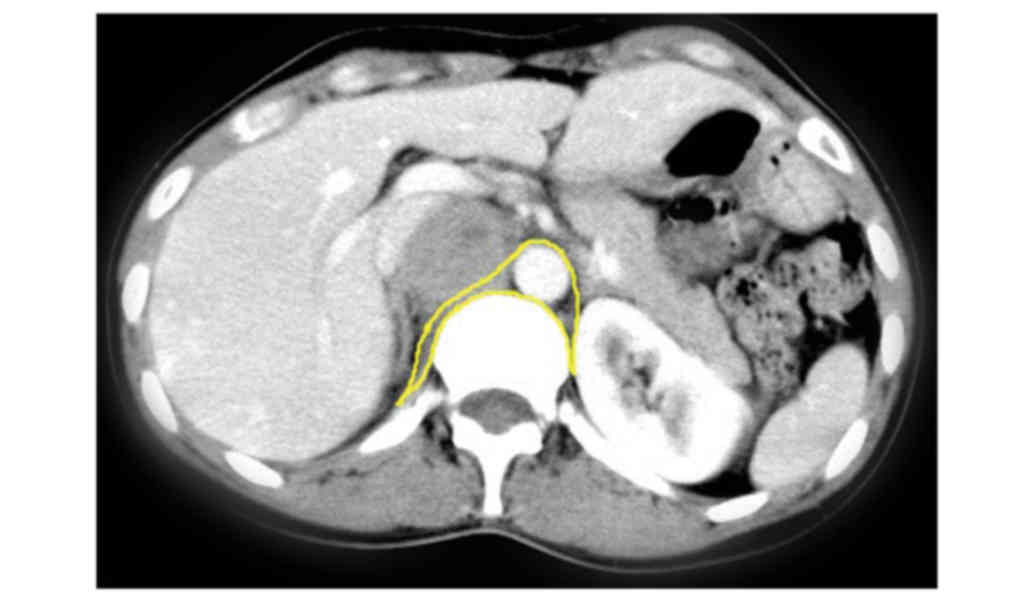

Tumor size and location

The mean maximal diameter of the 34 tumors was 8.7 cm (range, 3–25 cm). Fig. 2 summarizes the location of retroperitoneal paragangliomas in all 34 patients. A total of 33 retroperitoneal paragangliomas were located in association with the aorta and inferior vena cava, surrounding the adjacent renal vessels. The aforementioned tumors exhibited increased distribution on the left side (21 on the left side vs. 12 on the right side) and the tumor was located on the bottom of the pelvic cavity, lateral to the neck of the urinary bladder, in only 1 case. In the horizontal plane, retroperitoneal paragangliomas were located on either side of the aorta, behind the inferior vena cava, duodenum and pancreas (Fig. 3).

Figure 3.

Location of retroperitoneal paraganglioma in the horizontal plane. The area of retroperitoneal paragangliomas is highlighted in yellow and all the tumorsidentified in 34 cases were revealed to be within this area.

The present study, to the best of our knowledge, included the largest number of cases with retroperitoneal paragangliomas (n=34) with complete clinical data in the current literature. None of patients included exhibited a family history of paraganglioma, which is distinct from previous studies that have determined the association of paraganglioma with a family history (10,11). This distinction may be due to the inclusion of different ethnicities between studies. Although a previous study identified that retroperitoneal paragangliomas preferentially occurred in males (2), the present study revealed no predilection between sexes, which is similar to the study of Cunningham et al (1). In the present study, the tumor size ranged between 3 and 25 cm. The decreased tumor sizes were observed in the functionally active retroperitoneal tumors, which may be a result of early detection of tumors due to exhibition of endocrine symptomatology. All the tumors were located in the para-aortic plexus and primarily concentrated in the mesenteric artery region (Figs. 2 and 3). The tumors occurred on the left side at an increased frequency, which may be associated with the left slant of the abdominal aorta. In 4 cases, the tumor was identified to be posterior to the inferior vena cava, which may be due to the tumor originating from the para-aortic plexus. Tumors posterior to the inferior vena cava possesses the specific characteristics of retroperitoneal paragangliomas. Furthermore, retroperitoneal paraganglioma tumor sites are distant from the intervertebral foramen, which is distinct from other types of retroperitoneal neurogenic tumor.